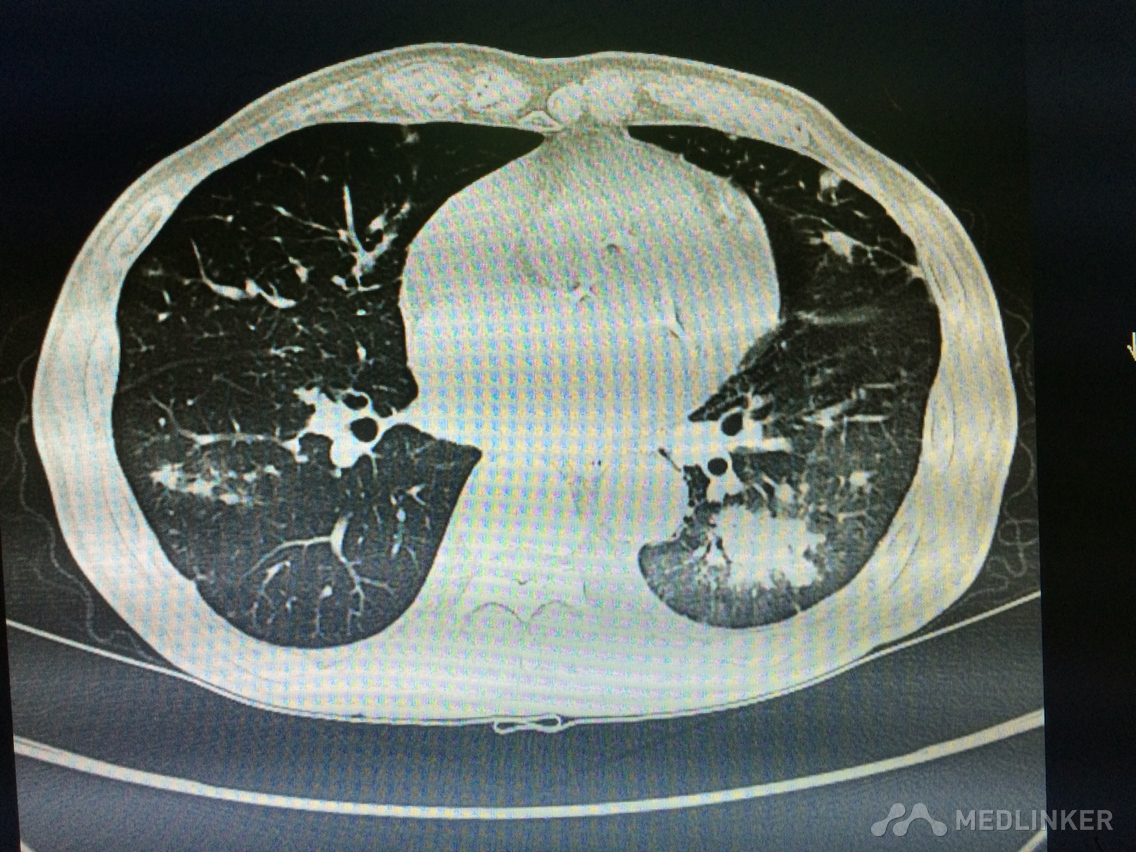

看这胸部CT?

咳嗽咳痰发热3天,伴胸痛气紧,偶痰中带血,体温38.7,伴全身乏力。

胸部!CT,,考虑什么?